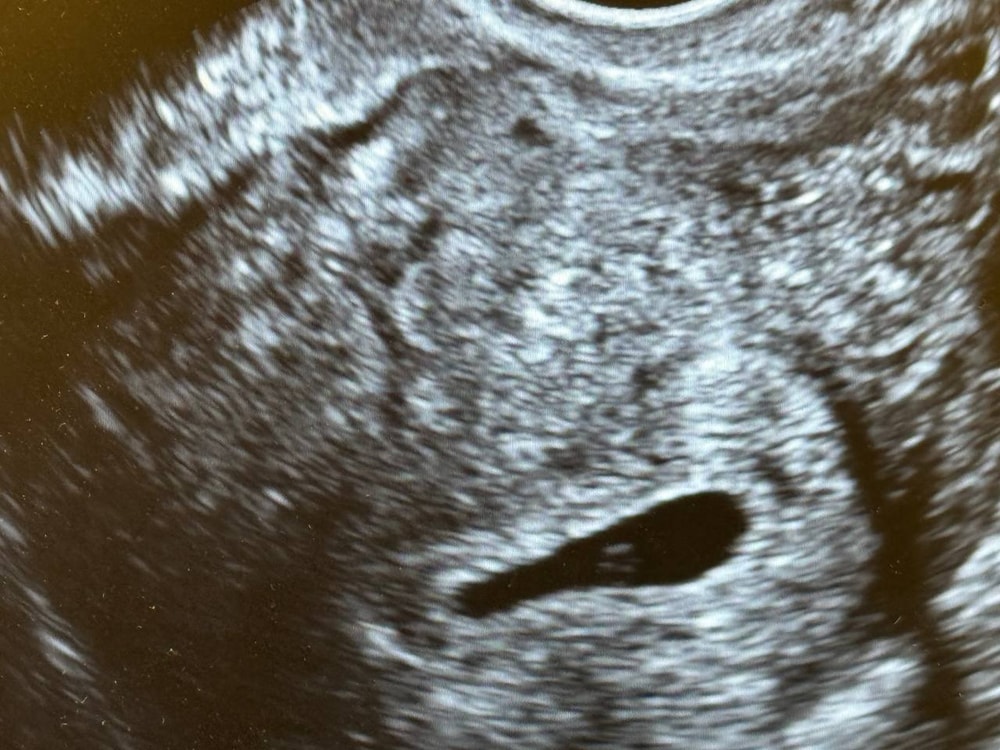

У меня один в один срок с вами, решила в этот раз подождать 8 недель и только потом идти на УЗИ. У многих девочек на форуме читала, что на сроке около 6 недель не видно ещё эмбриона.

Рановато. Как говорил мой гинеколог, когда есть желточный мешочек-это хороший признак ,значит эмбриончик появится скоро) может утешал так,не знаю. Была ровно в 5 недель, а в 5и5 недель уже нашли малыша в ПЯ. Сходите через недельку-полторы повторно

Так вам в заключении написали когда прийти на повторное УЗИ для подтверждения сердцебиения эмбриона. А так у вас всё хорошо маточная беременность раннего срока .

Еще слишком маленький срок. Не переживайте, сходите через неделю-две. Я в 5,2 делала, тоже только плодное яйцо. Сказали после 7 недель приходить. Пойду сегодня (ровно 8,0)

На 11 день задержки не увидите еще эмбрион и сб. Рано. Через неделю должно все уже быть

Пя нашли на вашем сроке-уже отлично)

Рано, в 6-7 недель видят эмбриошку и СБ.